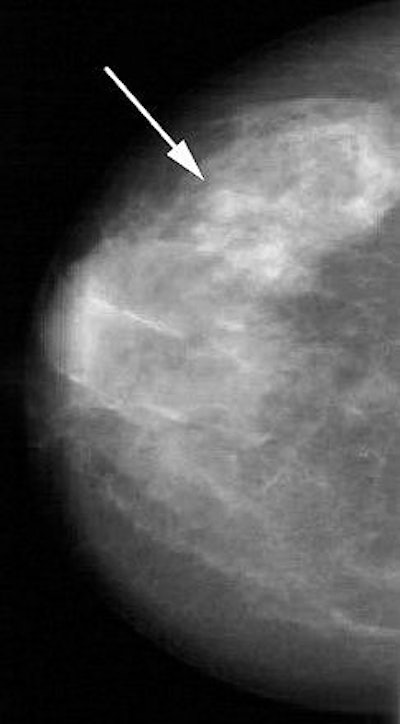

| Forty-five-year-old asymptomatic woman. Above, in left craniocaudal mammogram, arrow indicates mass in dense breast. Below, in left mediolateral oblique mammogram, arrow indicates mass in dense breast. Brem RF, Hoffmeister JW, Rapelyea JA, Zisman G, Mohtashemi K, Jindal G, DiSimio MP, Rogers, SK, "Impact of Breast Density on Computer-Aided Detection for Breast Cancer," (AJR 2005; 184: 439-444). |

This difference in CAD performance for dense and nondense breasts is significant because "CAD detection of masses is lower in dense breasts because of the greater 'background noise' and similar density of masses to the surrounding parenchymal density," the authors explained (AJR, February 2005, Vol. 184:2, pp. 439-444).